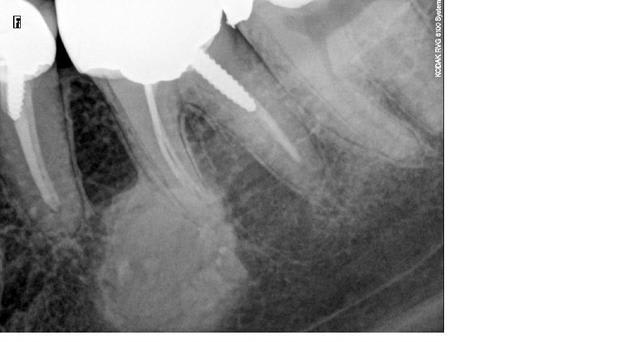

Cémentome?

Aucun signe clinique, découverte fortuite.

Cela pourrait être une "ostéite condensante apicale" selon une terminologie apprise lors du passage de mon CES d'endo. Ca se produit sur les dents jeunes, avec pulpite chronique. Mais je ne sais pas si en principe, elle ne régresse pas une fois le traitement canalaire accompli.

sachant que la patient a une quarantaine d'années, ne présente dans cette zone aucun signe clinique...

abstention et surveillance?